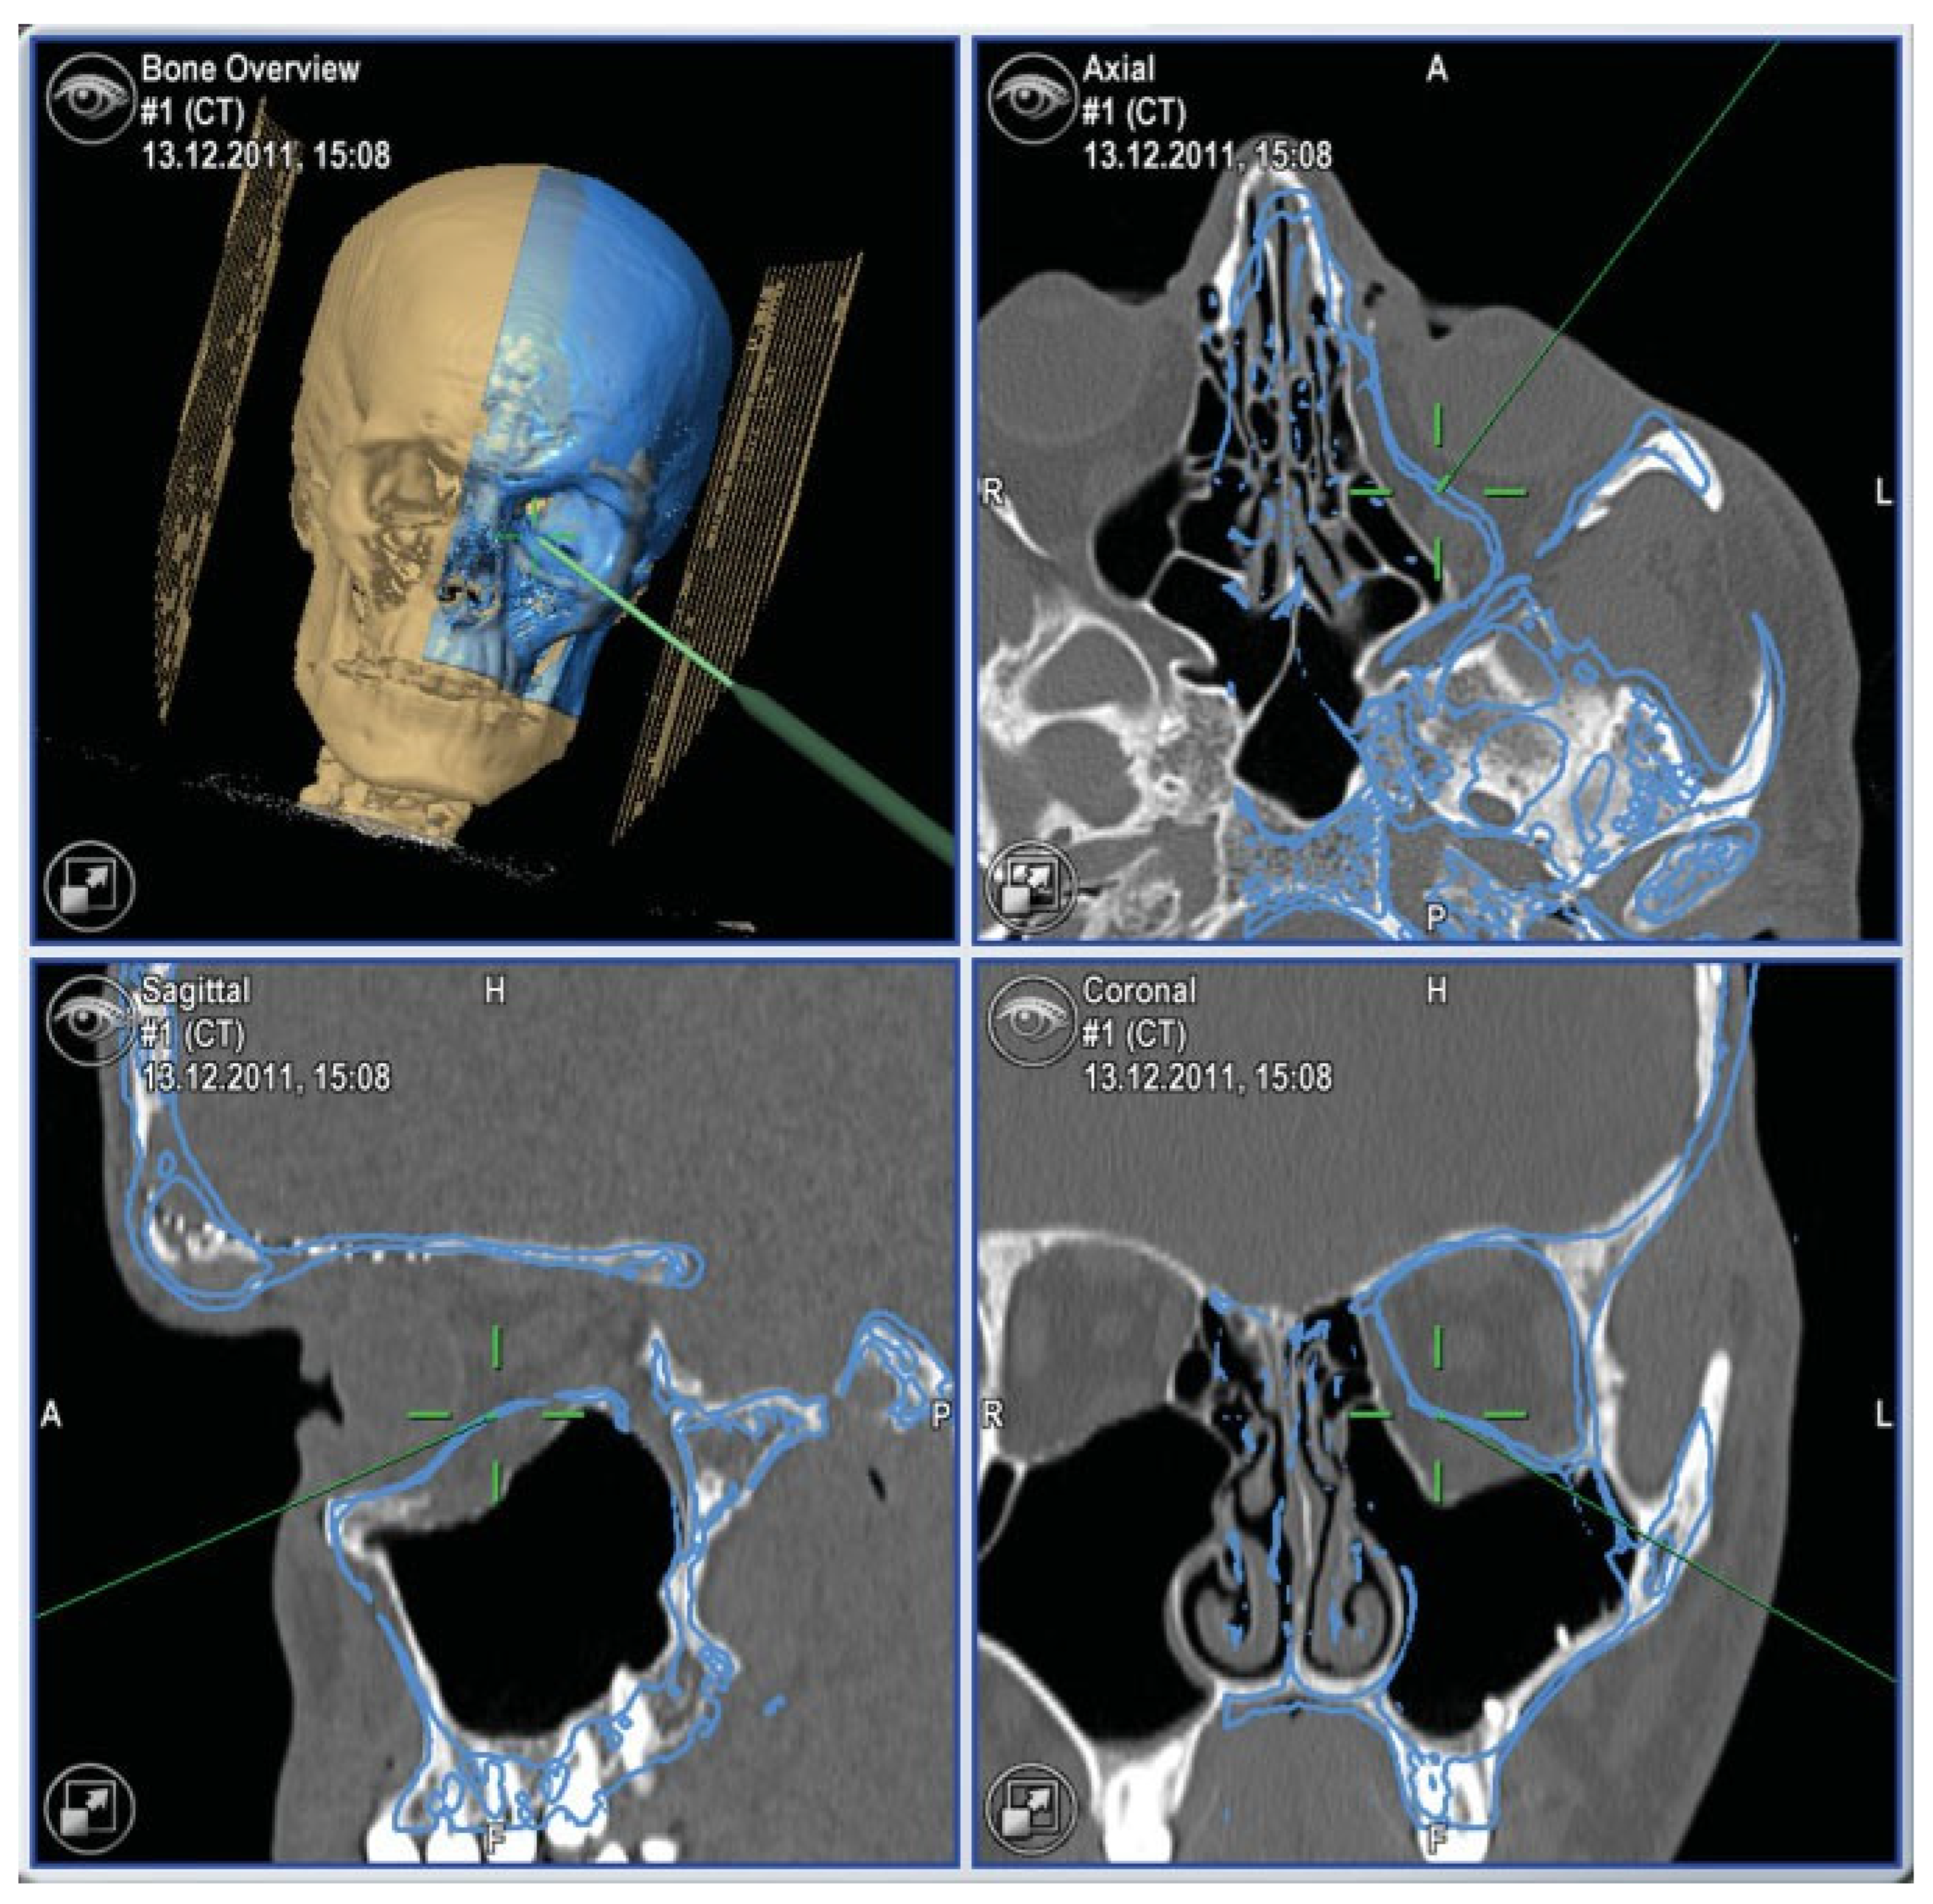

- In the case of optic canal decompression, postoperative evaluation of surgical outcome by using CT with axial and coronal thin-layer reconstructions is mandatory.